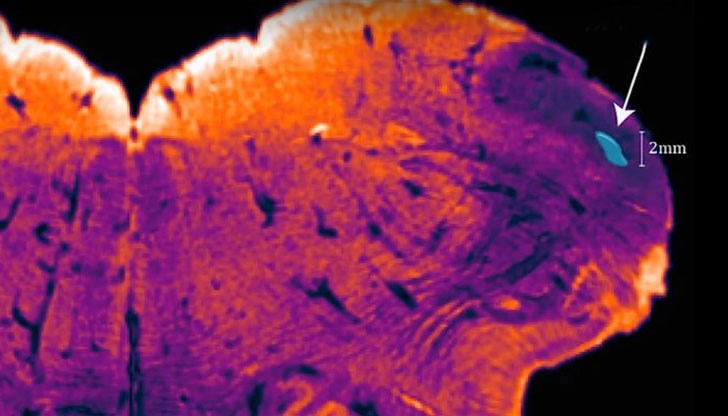

Учените от Австралийския изследователски институт (NeuRA) нарекоха откритието си endorestiform nucleus, тъй като мястото е разположено в долната част на мозъчния ствол. То се намира в основата на мозъка, където се свързва с гръбначния мозък и отговаря за нашата поза, баланс и движение.

Паксинос идентифицира тази част от мозъка с помощта на сравнително нова техника на оцветяване на мозъка, която сам е разработил, за да направи изображенията на мозъчната тъкан по-ясни за последния си атлас.

Тези оцветяващи елементи са насочени към активни клетъчни продукти - химически вещества в мозъка - невротрансмитери, които осигуряват карта на мозъчната тъкан. Това помага да се разделят групите неврони по функции, а не по външен вид. Използвайки такава техника, еndorestiform nucleus очевидно се откроява от останалите обекти - "оцветяването" се оказа по-плътно и околните области са представени в негатив. По този начин Паксинос прави откритието си.